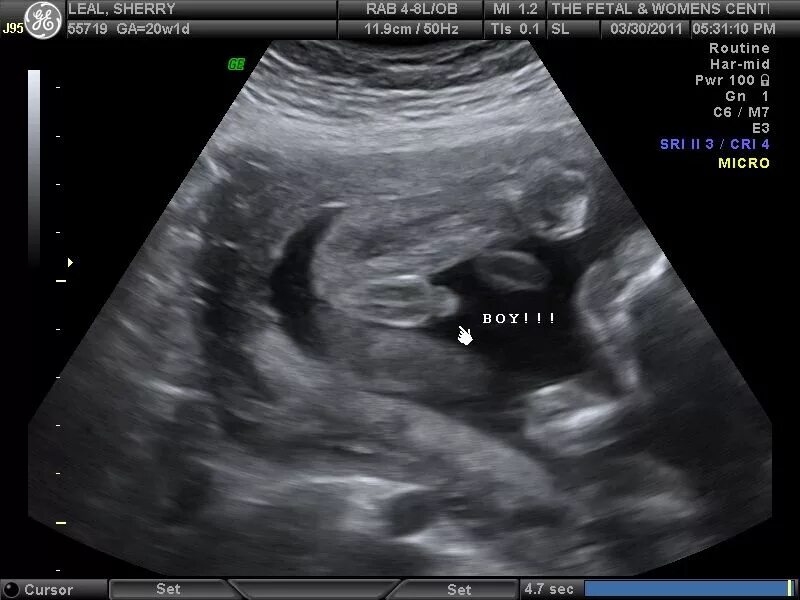

Может ли ошибки узи